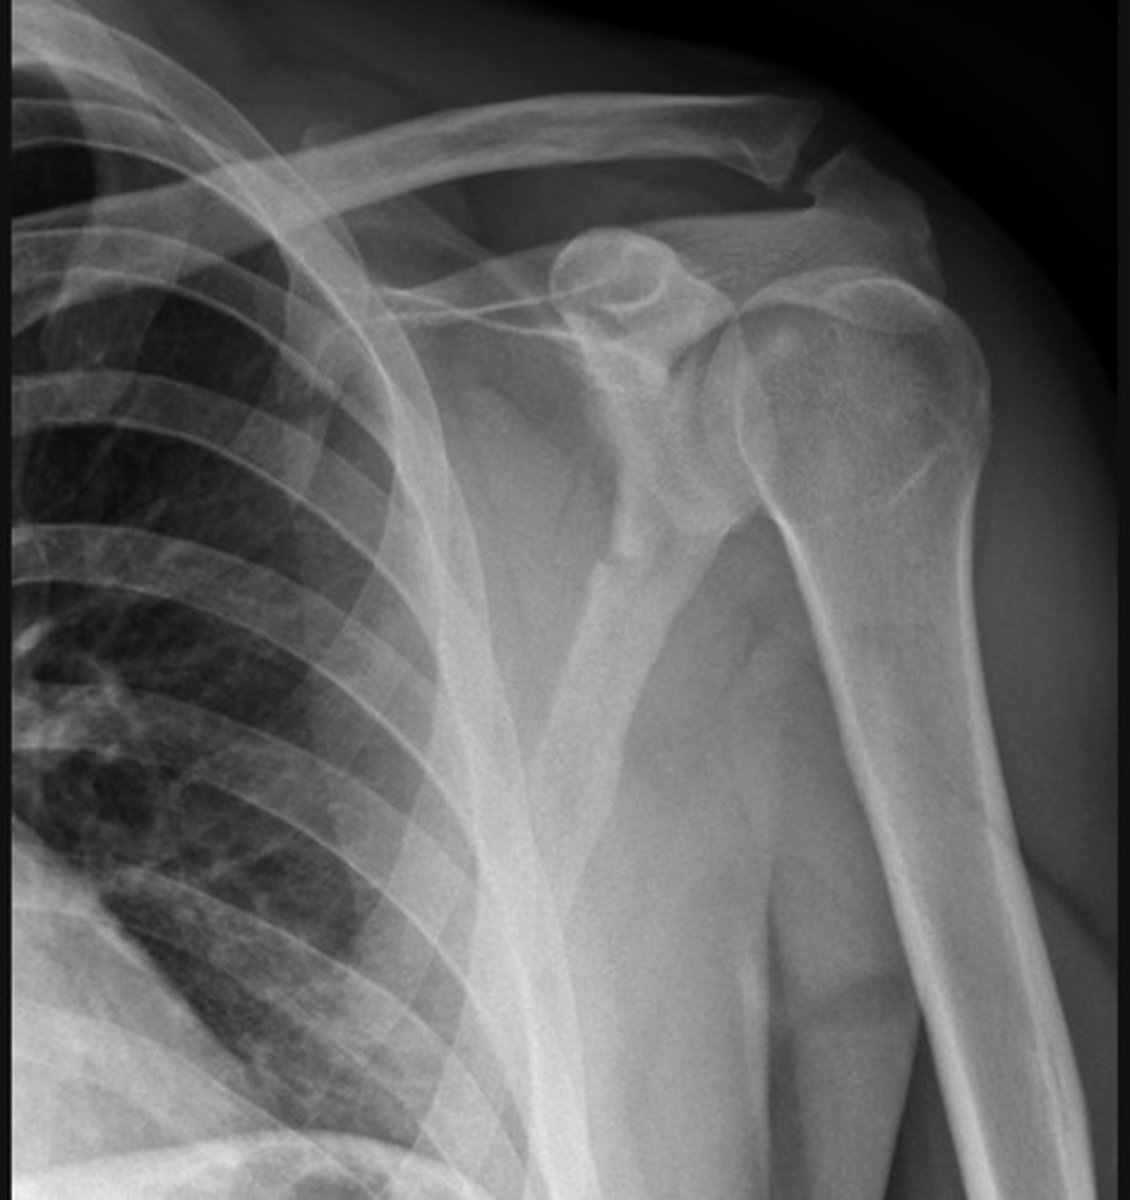

Anterior dislocation. The humeral head is dislocated from the glenoid of the scapula and is now located inferior to the coracoid process of the scapula.

This shoulder anterior dislocation is complicated by a greater tubercle fracture of the humeral head